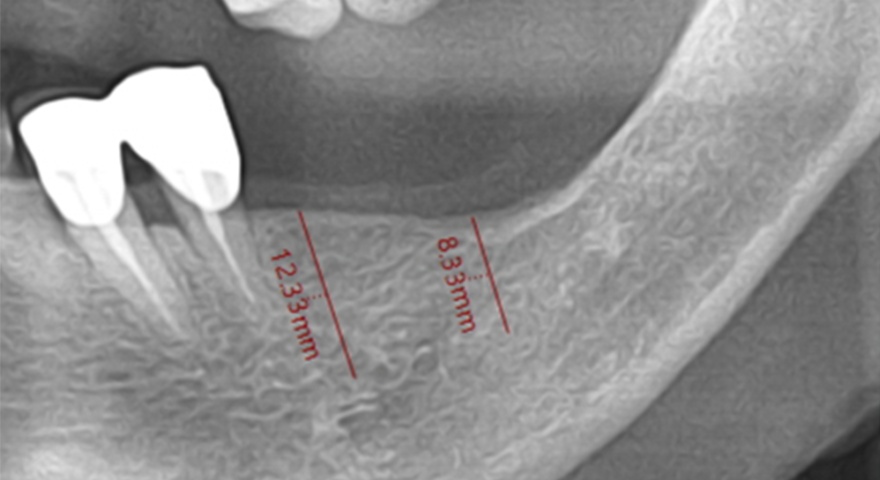

Проблема дегісценції кісткової тканини навколо імплантатів з боку щоки є актуальною, особливо в умовах обмеженого об’єму залишкової кістки. Це дослідження спрямоване на перевірку ефективності двошарового підходу до аугментації, що поєднує пастоподібний та гранульований ксеногенний матеріал, покритий колагеновою мембраною. Такий підхід застосували для відновлення ділянок оголеної різьби імплантатів. У дослідженні взяли участь троє пацієнтів, для аналізу було відібрано три імплантати. Середній показник BIC сягнув понад 67 %.

У рамках проспективного дослідження троє пацієнтів із частковою або повною адентією отримали загалом 17 імплантатів, з яких три — в ділянки з вираженими дефектами букальної кістки. Ці імплантати були вилучені через шість місяців для аналізу. При аугментації застосовували формопластичний остеоматеріал (S1) та гранульований матеріал (BOSS), які покривали колагеновою мембраною (COLLA). Всі матеріали були бичачого походження. Стан кісткової інтеграції аналізували гістологічно та гістоморфометрично.

Фото до операції

Передопераційний панорамний знімок

9) 2 мм букальна дегісценція

12) Післяопераційний КТ знімок